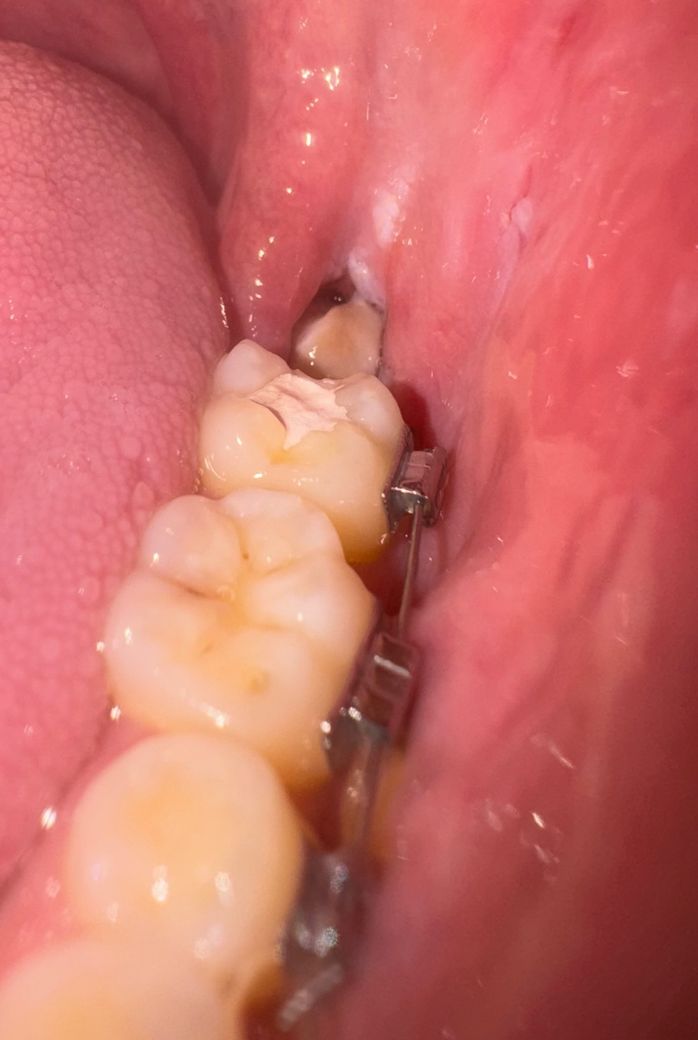

사랑니 뽑은지 3일차 입니다 혹시 드라이 소켓일까요?

사랑니 뽑은지 3일치 입니다 드라이소켓 증상 중 통증이 심하다던데 약간 열감이 있는 정도입니다

사진으론 잘 안 보이는데 좀 더 깊고 안에는 조금 검은색입니다..

드라이소켓 증상은 다양합니다. 극심한 통증, 악취 내지는 회색빛 지저분한 양상의 잇몸 불완전 치유를 보입니다. 사진상이나 증상으로 봤을때 드라이소켓과는 거리가 있어보입니다.

사랑니 발치한곳에 음식물이 들어가 잇는 상태 같습니다. 치과에 가셔서 소독을 한번 받아보시는게 좋을것같습니다.